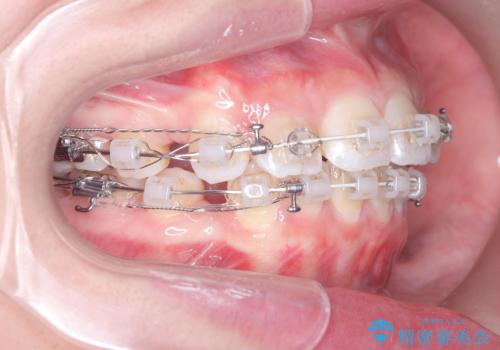

突き出た前歯を下げて理想的な横顔に。上下左右4番抜歯による審美ワイヤー矯正

精密検査の結果、歯を後方へ下げるためのスペースが不足していたため、上下左右の4番目の歯(第一小臼歯)を計4本抜歯する計画を立案しました。抜歯によってできたスペースを最大限に活用し、前歯を後ろに下げることで、口元のボリュームを抑え、バランスの良いEライン(横顔のライン)を目指すこととしました。装置は、日常生活で目立ちにくい審美ワイヤーを選択しました。

治療は、審美ワイヤーを用いて抜歯スペースを徐々に閉じながら、前歯の角度と位置を精密にコントロールして進められました。ワイヤー矯正は歯を三次元的にしっかりと動かすことができるため、前歯を単に倒すのではなく、根元から理想的な位置へと誘導しました。

1年半の治療期間を経て、抜歯したスペースは完全に閉じ、突き出ていた前歯はすっきりと内側に収まりました。噛み合わせの精度も向上し、機能面でも良好な結果が得られています。